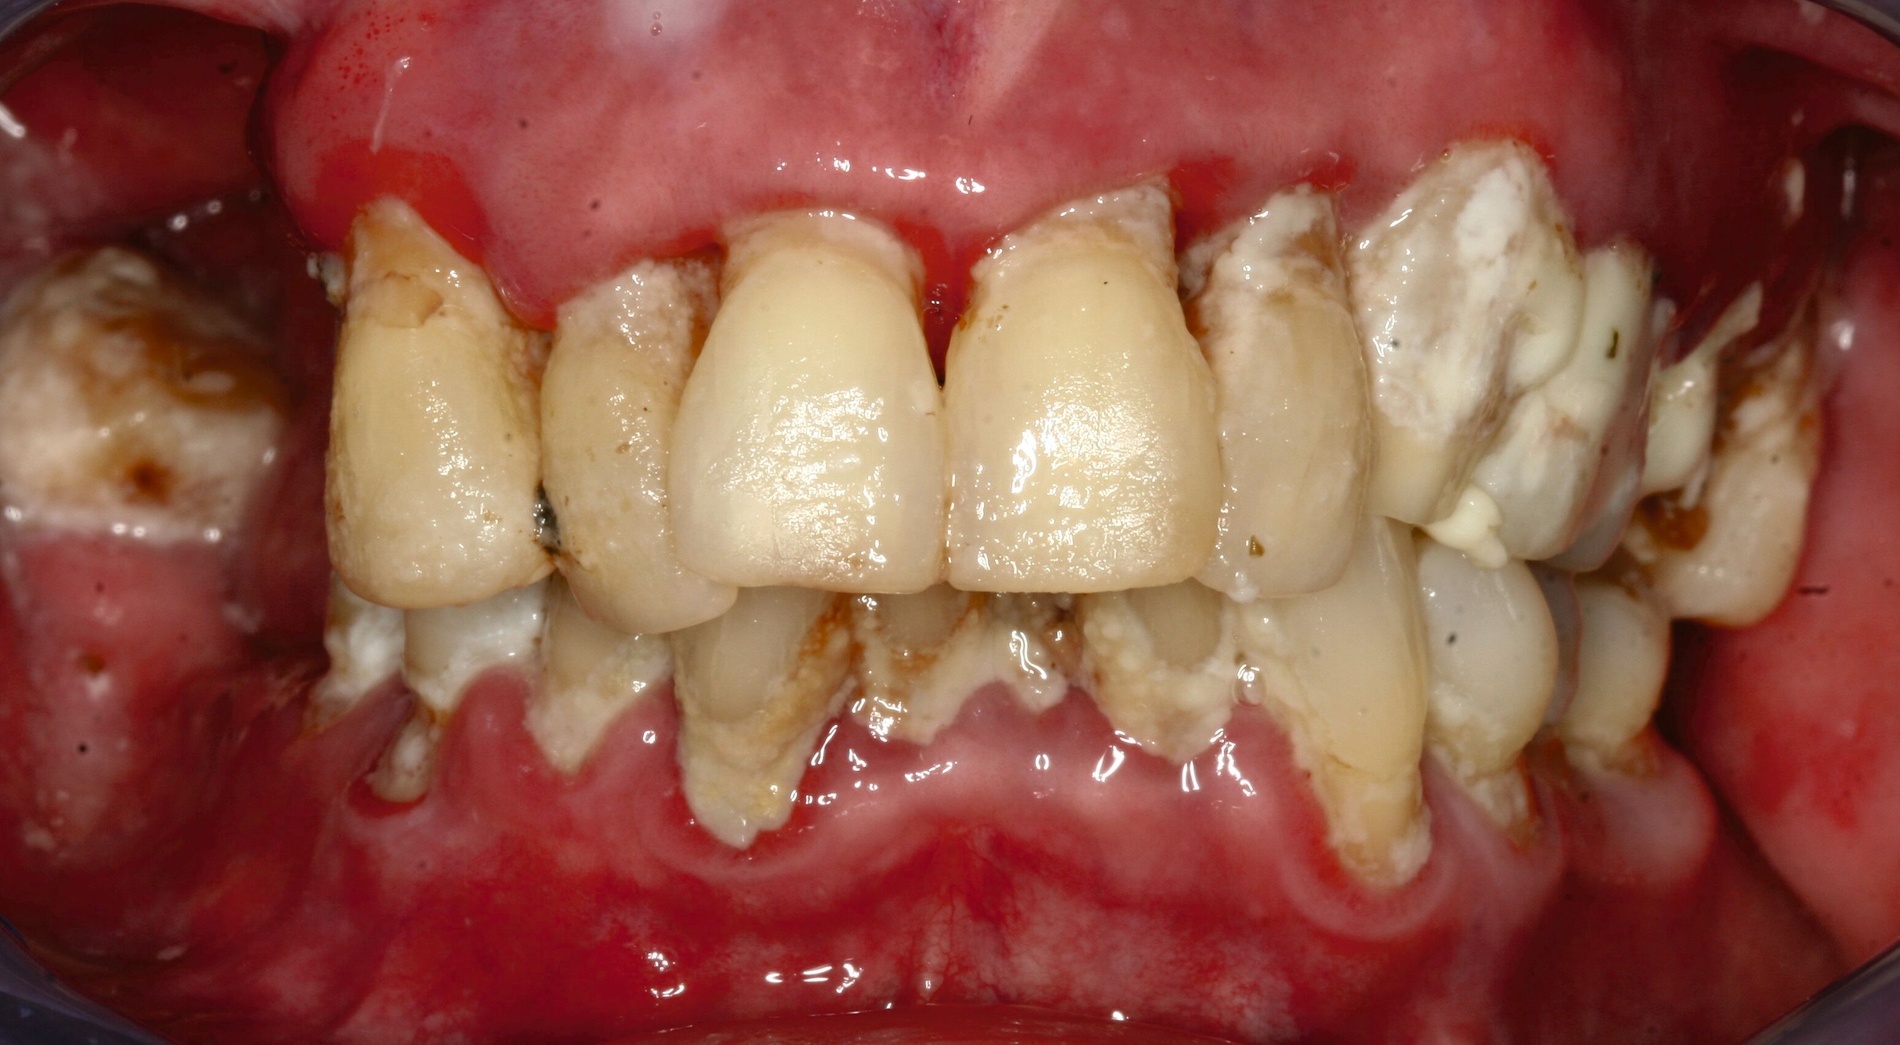

Eine 74-jährige Patientin erhielt eine Modellgussprothese im Oberkiefer zur Abdeckung einer Mund-Antrum-Verbindung infolge der Resektion eines malignen Befunds im Bereich des Alveolarfortsatzes rechtsseitig (Abbildung 1). Trotz mehrfacher Umarbeitungen gelang eine Adaption an den Zahnersatz nicht. Die Patientin empfand die Klammern als zu scharf und spitz. Zudem störte sie sich an der Ästhetik. Die Mundhygiene war gut, nur wenige Zähne besaßen eine Füllung. Es bestand eine hohe Erwartungshaltung an den Zahnersatz.

Bezogen auf die Belastbarkeit lagen zum damaligen Zeitpunkt trotz der Malignomtherapie keine Einschränkungen vor (BS 1). Dem Wunsch der Patientin nach einem Klammer-freien Zahnersatz konnte mit regulärem Therapieaufwand entsprochen werden (Abbildung 2). Nach dessen Eingliederung gelang eine rasche Gewöhnung. Die Patientin erschien viele Jahre regelmäßig zur professionellen Zahnreinigung und zur Kontrolle. Zahnmedizinische Interventionen waren nicht erforderlich.